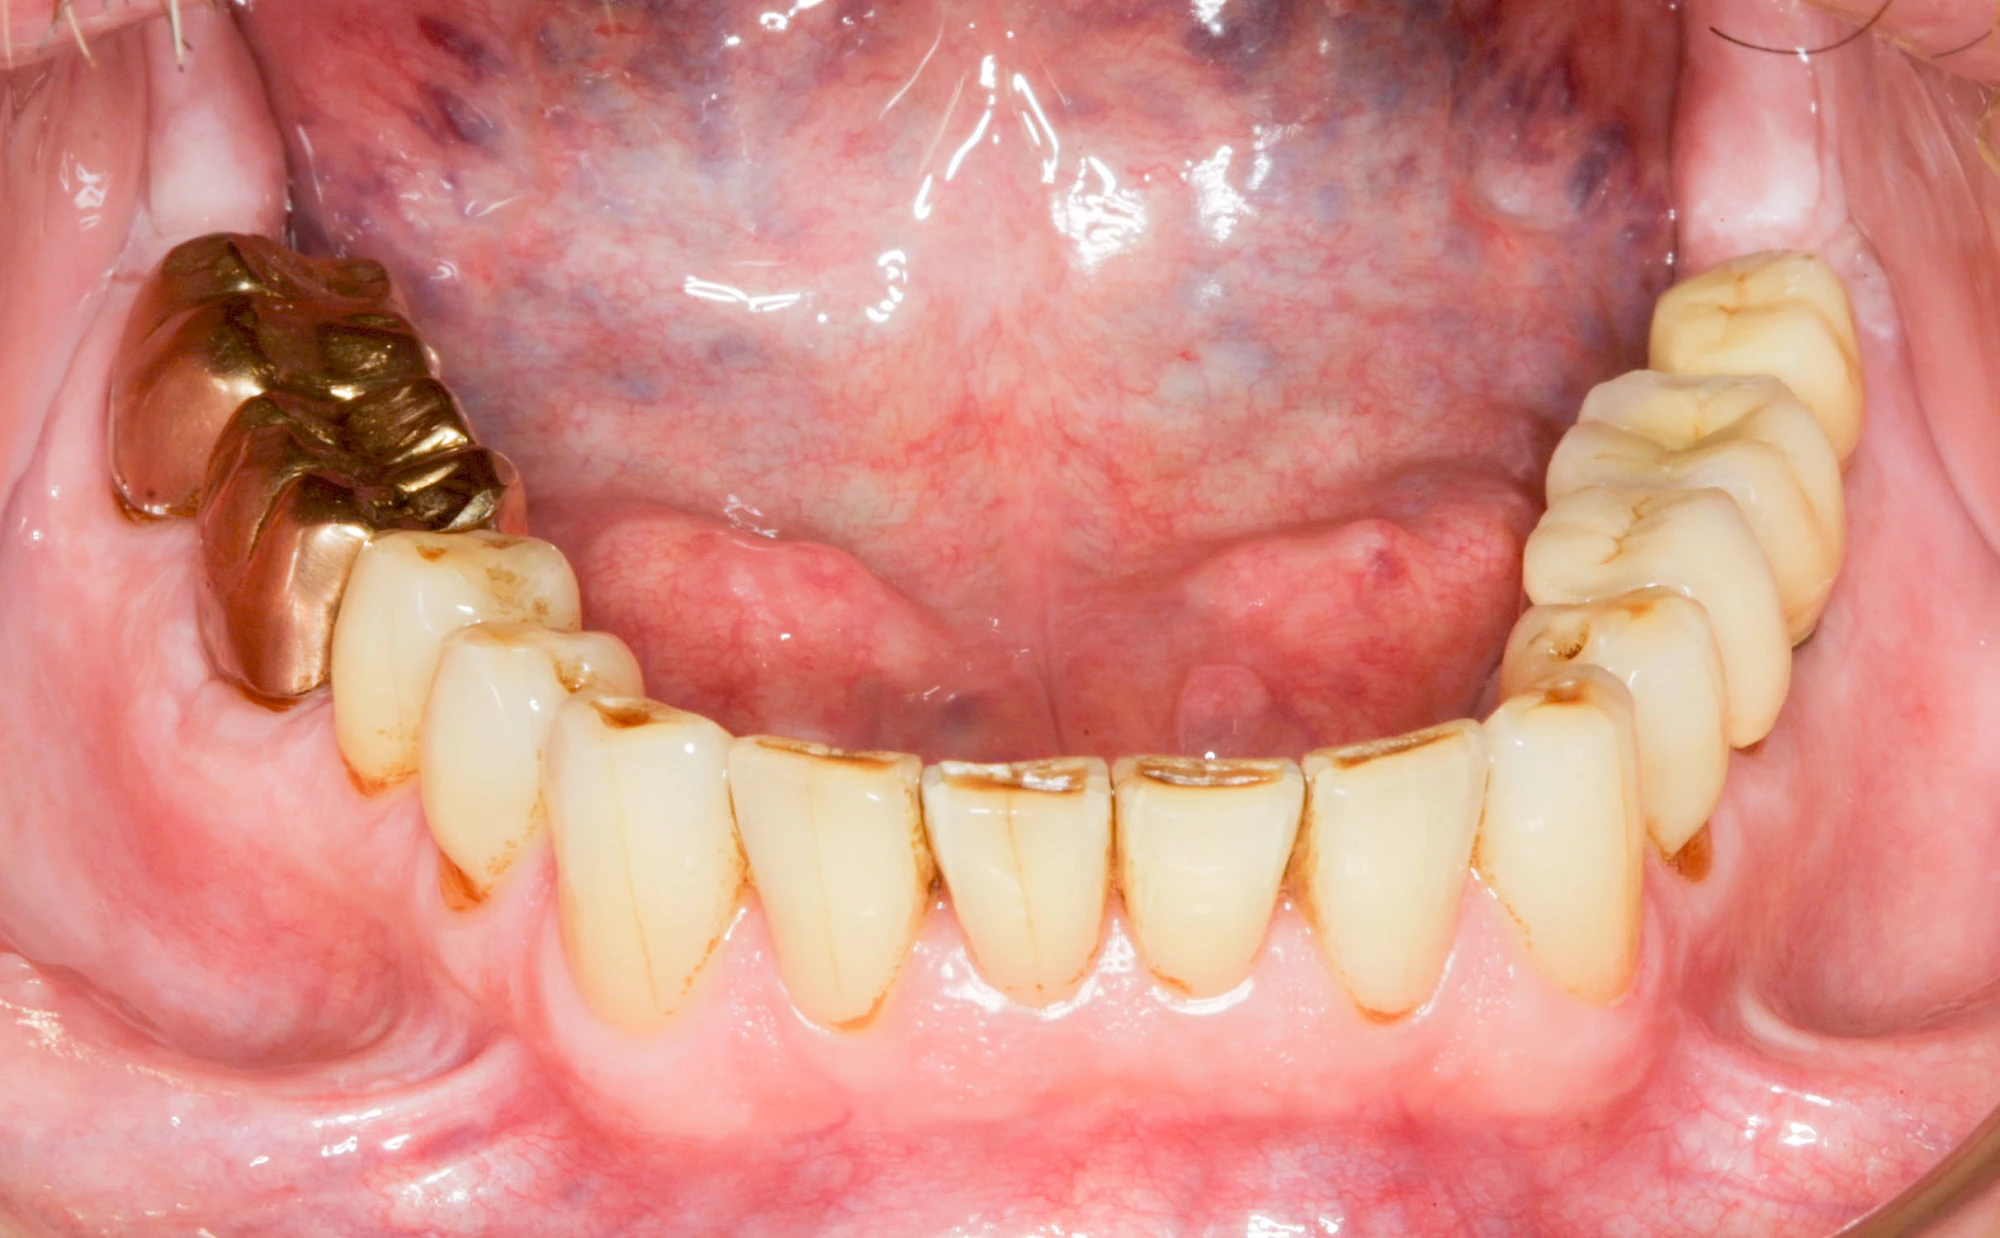

Fehlen einzelne Zähne und die Nachbarzähne sind unbeschadet oder gut zahnärztlich versorgt, werden immer häufiger Implantate gewählt, um die Lücken zu schließen. Auch bei größeren oder verteilten Lücken, wenn keine herausnehmbare Prothese gewünscht ist, werden Implantate für Kronen- bzw. Brückenversorgungen gesetzt. In Einzelfällen entscheiden sich sogar zahnlose Patienten für eine festsitzende Versorgung auf Implantaten.